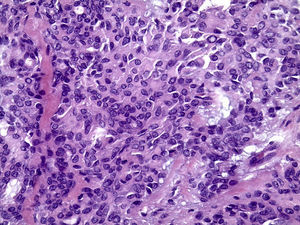

O exame histopatológico apresenta neoplasia geralmente bem delimitada por cápsula de tecido conjuntivo fibroso, com parênquima constituído por células epiteliais ductais e células mioepiteliais. Essas células frequentemente exibem diferentes morfologias gerando arquiteturas teciduais distintas dentro do mesmo tumor, motivo pelo qual foi denominado pleomórfico2,3. Podem ser encontradas áreas ductiformes, sólidas, mixoides, hialinas, plasmocitoides, osteoides e condroides, além de metaplasia escamosa6,7.

Os cortes histológicos, corados em hematoxilina e eosina, mostraram neoplasia de glândula salivar benigna, constituída por células epiteliais e mioepiteliais, parcialmente envolvida por fina cápsula de tecido conjuntivo fibroso (fig. 5). As células epiteliais encontravam‐se formando lençóis ou estruturas ductiformes, enquanto as células mioepiteliais formavam áreas mixoides, hialinas (fig. 6) ou exibiam aspecto plasmocitoide (fig. 7). O diagnóstico de adenoma pleomórfico foi confirmado. Paciente queixou‐se de desconforto no palato quando se alimentava, durante as 2 primeiras semanas após cirurgia. O paciente está sendo acompanhado clinicamente e, 2 anos após a cirurgia, não apresenta sinais de recidiva da lesão (fig. 8).

Os cortes histológicos mostraram neoplasia benigna de glândula salivar, envolvida por cápsula de tecido conjuntivo fibroso (fig. 14). O parênquima neoplásico é constituído por células epiteliais dispostas em lençóis e estruturas ductiformes, além de células mioepiteliais formando áreas mixoides e hialinas (fig. 15) ou apresentando‐se com morfologia plasmocitoide (fig. 16). O diagnóstico de adenoma pleomórfico foi confirmado. A paciente relatou ausência de dor no pós‐operatório e manteve utilização da placa de acrílico por 4 semanas. A paciente encontra‐se em acompanhamento e o exame clínico após 2 anos da remoção cirúrgica mostrou adequada cicatrização e ausência de sinais de recidiva da lesão (fig. 17).